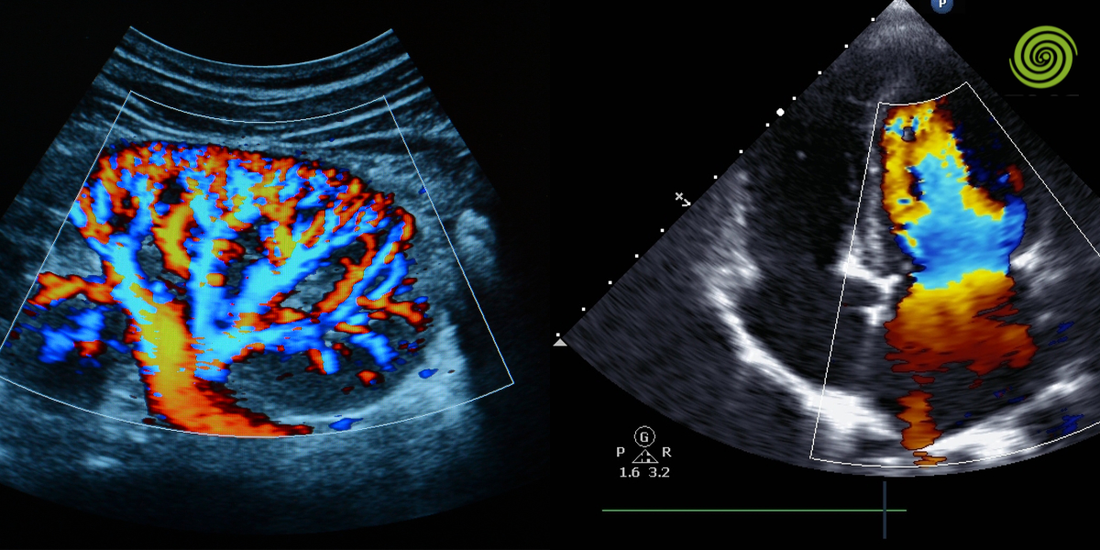

Doppler color: Más allá de la estética visual

El Doppler color actúa como nuestro mapa de navegación. Sin embargo, en la gestión B2B de tecnología, debemos evaluar el "color box" y cómo este afecta la resolución temporal. Un error común es trabajar con cajas de color demasiado grandes que ralentizan el procesador, introduciendo un retraso (lag) que imposibilita la sincronización exacta entre el pulso del paciente y la imagen en pantalla.

• Persistencia del color: Que no "manche" las paredes del vaso (bleeding), lo cual es crucial para medir la luz real remanente en una placa excéntrica.